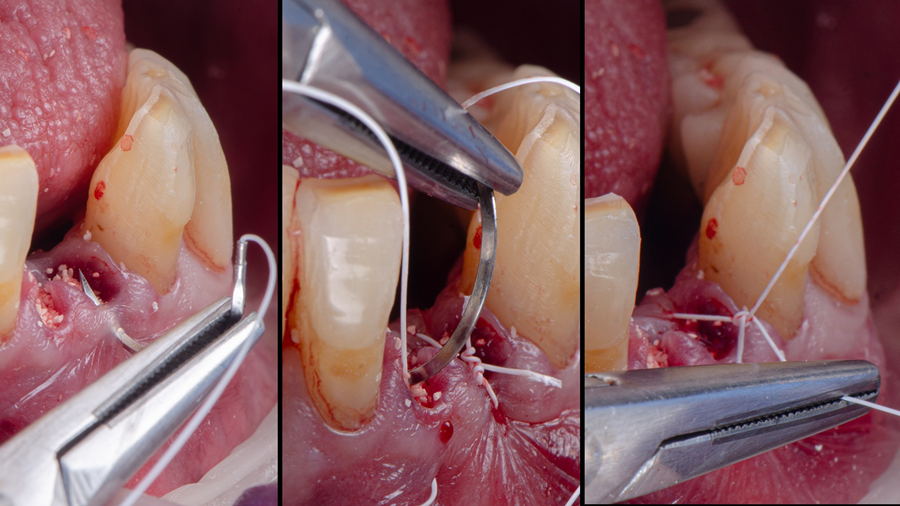

Sutura e provisório pós-operatório

Após o preenchimento dos GAPs com enxerto, foi realizada a sutura visando estabilizar os tecidos e proteger o coágulo. Utilizou-se fio de PTFE (politetrafluoretileno) monofilamentar (Cytoplast – Implacil Osstem), material não reabsorvível altamente indicado em situações de tecidos finos ou áreas de regeneração óssea. Esse tipo de fio de sutura apresenta baixa aderência bacteriana e é biologicamente inerte, gerando mínima reação inflamatória nos tecidos. Tais propriedades são desejáveis para garantir uma cicatrização previsível, pois reduzem o risco de infecção do sítio cirúrgico e evitam isquemia marginal por excesso de tensão. O fio de PTFE também possui superfície lisa (baixo coeficiente de atrito) e boa maleabilidade, deslizando facilmente no tecido e facilitando a obtenção de nós firmes. No presente caso, isso permitiu manter as papilas suturadas com estabilidade, sem irritação aos tecidos – uma consideração importante dada o periodonto fino da região anterior inferior.